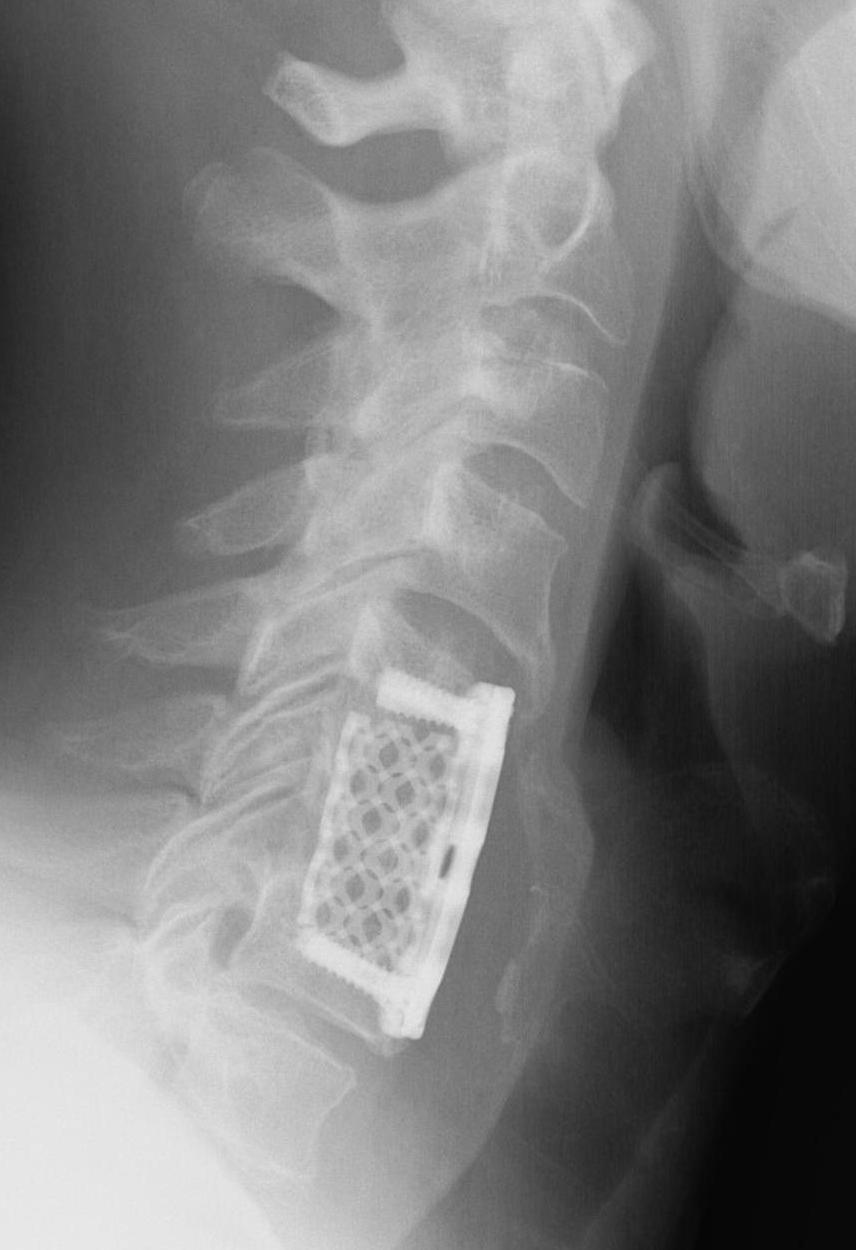

ACDF

Indication

Anterior cord compression

Single or double level compression

Kyphotic deformity

Advantages

Removes entire disc

Maintain / restore lordosis

Disadvantages

Difficulty decompressing the nerve roots in foramen

Difficult to decompression vertebral bodies

Relatively contra-indicated with OPLL